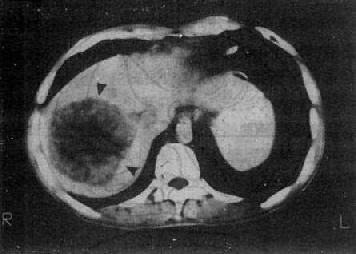

2.海绵状血管瘤 CT平扫表现为类圆形低密度区,境界较清楚,密度较均匀。较大的血管瘤,其中心部分呈更低密度区,平扫所见难于肝癌鉴别。增强扫描尤其是动态扫描是鉴别诊断的必要手段,而以且注射和扫描技术起决定性作用。以60%~70%泛影葡胺60ml于30秒内注入静脉,注射完毕立即对病区层面进行扫描,然后在1、3、5分后再对病区层面扫描,必要时最后一次扫描可延迟到注射后10~15分。在注射造影剂60秒内的扫描片上,血管瘤边缘出现结节状,高密度的增强灶,代表瘤中的“血窦”,其密度与主动脉的密度相近,明显高于正常肝。在其后的扫描片上,可见增强的范围逐渐向中心扩展,而增强灶的密度则逐渐减低,最后整个血管瘤被造影剂“填满”,即整个血管瘤与肝的密度相等。这个过程约为几分钟到10~20分钟。造影剂在血管瘤内持续时间长,是与肝癌鉴别的重要征象。较大的血管瘤,其中心可始终保持低密度(图4-3-7)。

肝血管瘤

图4-3-7 肝血管瘤

CT增强扫描,注射造影剂后10分钟,可见原来两个低密度

区被造影剂基本完全充盈(↓)。图为两个相邻层面